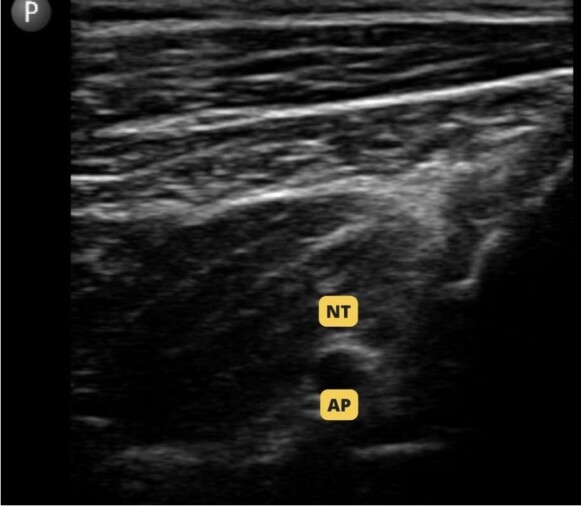

Orthopedic procedures are associated with severe postoperative pain. In TPLO, the block commonly used is the sciatic nerve block associated with the femoral nerve block. In orthopedic surgeries in human medicine, the iPACK block associated with the adductor canal block has been used as alternatives that do not affect the strength of the quadriceps femoris muscle. The objective of this study was to evaluate the trans and postoperative analgesic effect of the association of iPACK block and adductor canal block, as well as to evaluate the patient's motor recovery after surgery. Four patients were selected, without distinction of breed and gender, weighing more than 22lb, referred to TPLO. All patients underwent the combination of iPACK block and adductor canal block with 0.5% bupivacaine. The intraoperative evaluation was carried out by measuring mean arterial pressure, heart rate and respiratory rate, and all patients were stable during the procedure. The postoperative evaluation was carried out based on the assessment of pain using the modified Glasgow scale, in which all patients scored less than 05/24, and assessment of ambulation through videos using the adapted Muzzi scale, presenting ambulation between grade 1 and 2. No patient required intraoperative or postoperative analgesic rescue.